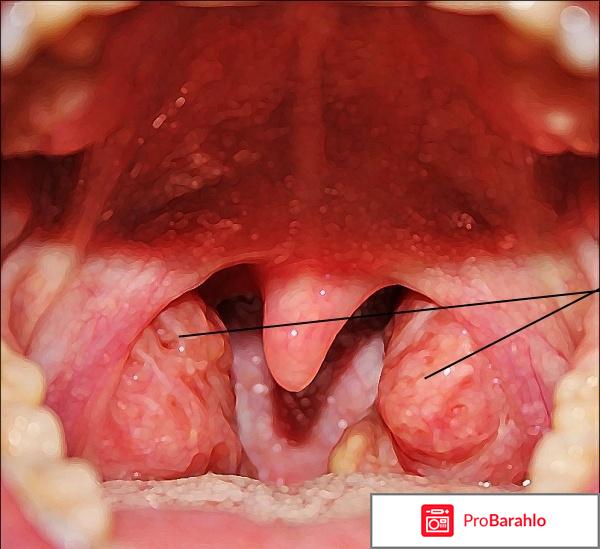

Долго думала, писать ли этот отзыв, и все таки решилась. В отзыве хочу рассказать о препарате, который носит название Имудон.

Имудон это препарат, который по идее должен помочь справится с частыми болезнями, особенно если это касается горла, носа и так далее.

Имудон мне посоветовал врач, к которому я обратилась. Он назначил пропить курс препарата, и тогда прийти повторно на прием, для того, чтобы подытожить был ли эффект от препарата.

Таблетка не большого размера, круглая, белого цвета. Ее нужно не пить, а рассасывать в ротовой полости. То есть положить ее в рот и дождаться, пока она полностью растает.

хронический тонзилите

фарингит

Как видите, спектр приема такого средства очень большой, потому таблетки назначаются довольно часто.